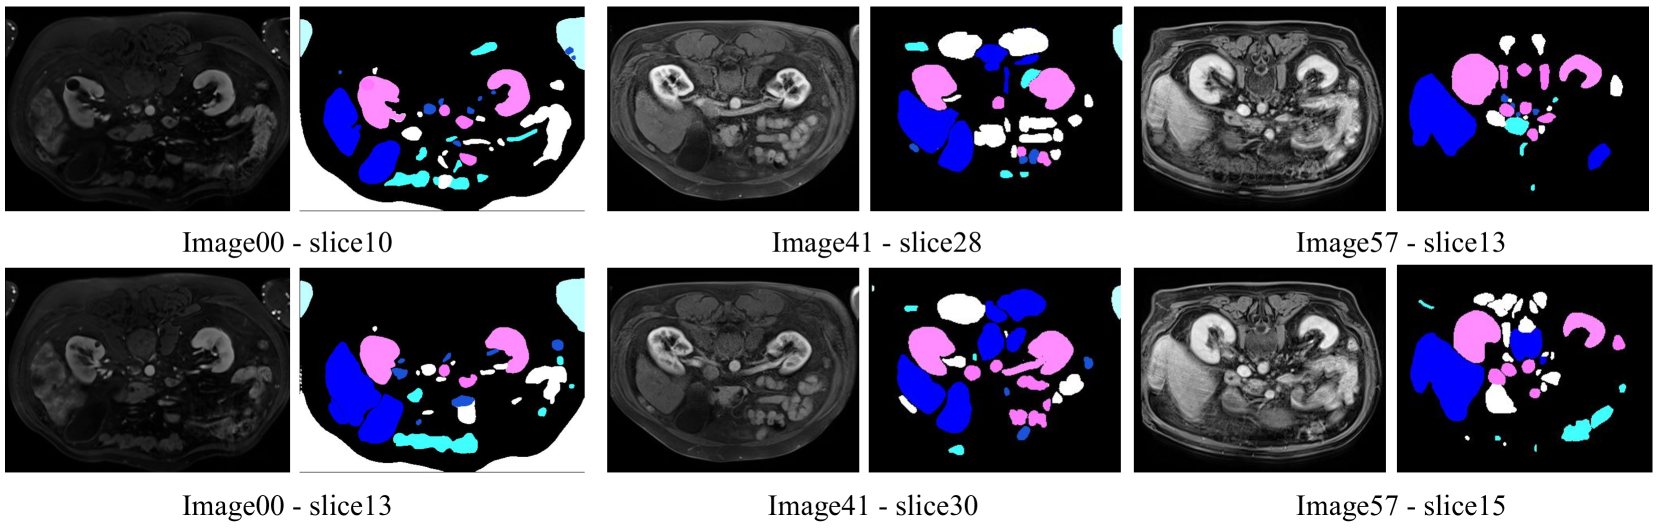

Generalization on Medical Domain: an External Validation Study

To further validate the generalization of ALPS on medical domain, we have utilized the ATLAS2023 dataset (Quinton et al. 2023), a resource within the medical segmentation domain, to evaluate the efficacy of our ALPS for unsupervised auto-labeling of medical images. The ATLAS2023 dataset, designed for the automatic segmentation of tumors and livers, comprises T1 CE-MRI liver scans from 90 patients with unresectable liver cancer and 90 corresponding liver and liver tumor segmentation masks. These are divided into training and testing cohorts, consisting of 60 and 30 patients respectively. Given that the CE-MRI images (utilizing a gadolinium contrast agent) from the ATLAS dataset were acquired on five Siemens 3T and 1T MRI machines, this 3D MRI data is not directly applied to the vanilla SAM. To address this, we initially design a script to convert 3D MRI data into 2D PNG format, prior to implementing our framework for automatic annotation. The qualitative results are shown in Fig 5. From the visualization results, we can observe that our proposed framework, designed for 2D slices of MRI data, demonstrates effective segmentation of liver and kidney. Furthermore, the color mapping within the framework accurately corresponds to the designated colors (pink for kidney and blue for liver) across multiple images. Due to the weak texture feature information of images, there may be unrelated instances that have been assigned to error labels. However, the label assignment for primary instances also maintains higher accuracy.

Refer to caption

Figure 5: Some examples of Pseudo-Labeled results on ATLAS2023 dataset.

To validate the pseudo-label ATLAS 2023 dataset (ATLAS-PL) we constructed, we selected mainstream methods for pre-training and fine-tuning, respectively. Specifically, we separately chose DoDNet (Zhang et al. 2021), MED3D (Chen, Ma, and Zheng 2019), and SAM-Med2D (Cheng et al. 2023a) for experimental validation. The experimental results are shown in Table 6, we can observe that after pre-training on our constructed ATLAS-PL, the performance of the above three methods has been significantly improved in both DSC and mIoU metrics. Specifically, for DoDNet, the DSC for Tumor increased by 5.37% and the mIoU by 4.78%. For MED3D, the DSC for Liver increased by 1.63%, and the mIoU by 1.07%. For SAM-Med2D, the increases in DSC and mIoU on average are 0.96% and 0.98%, respectively. We can attribute this significant improvement to our proposed ALPS framework, which can fully utilize the ability of vanilla SAM and generalization of online K-means to predict pseudo-label without medical prior for later pre-traning phrase.